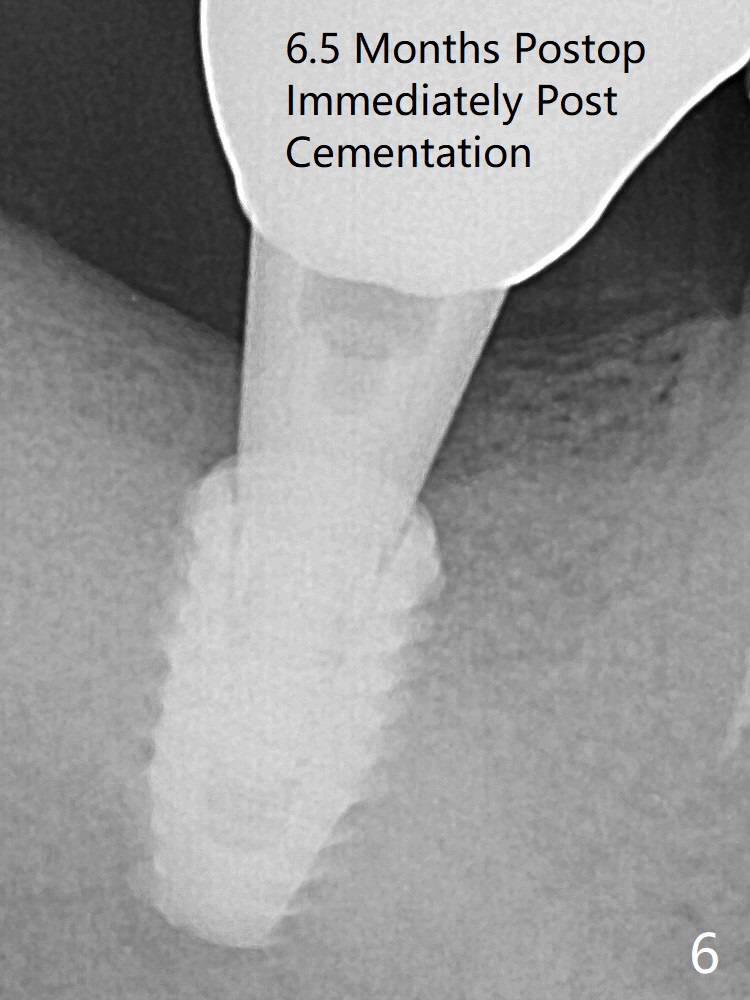

A 5x8.5 mm implant achieved primary stability in the final 1-2 mm. The implant was then placed ~ .5 mm deeper (~ 40 Ncm) (Fig.1). The implant, apparently having been osteointegrated 5.5 months postop (Fig.3), was placed deep, probably related to pressing the distal end of the guide too heavily. It is difficult to restore with use of a 5.2x5.5(5) mm abutment. There is apical bone loss (arrowheads), most likely due to the dense bone and heat during osteotomy. Immediately post cementation PA confirms the implant distal placement (Fig.6). The trajectory is not right, since no matter how the sensors are placed, the implant threads cannot be shown clearly (Fig.10), in consistence with the distolingual access hole (Fig.11).